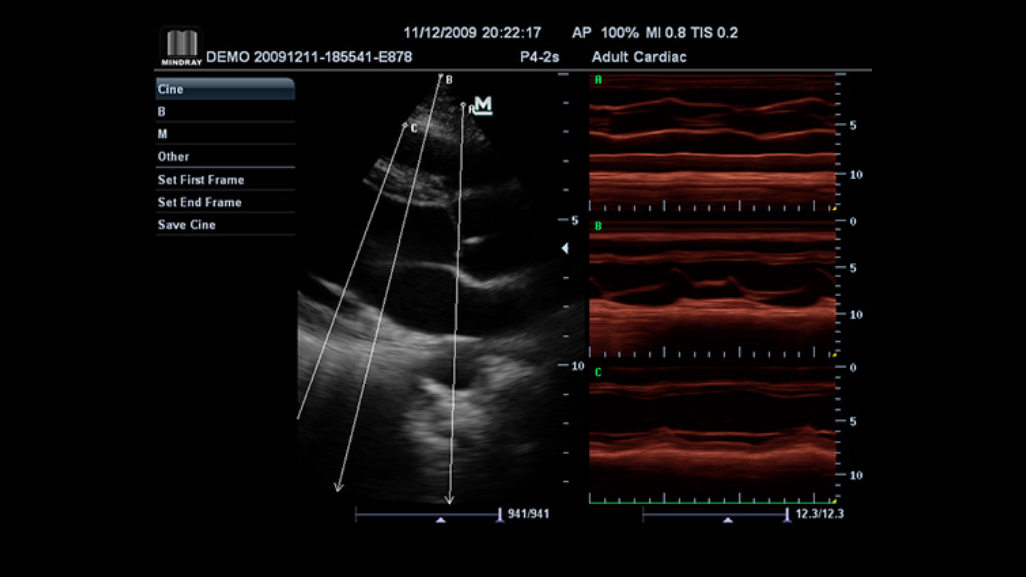

iZoomTM

Gain instant full screen view on the click of a single key.